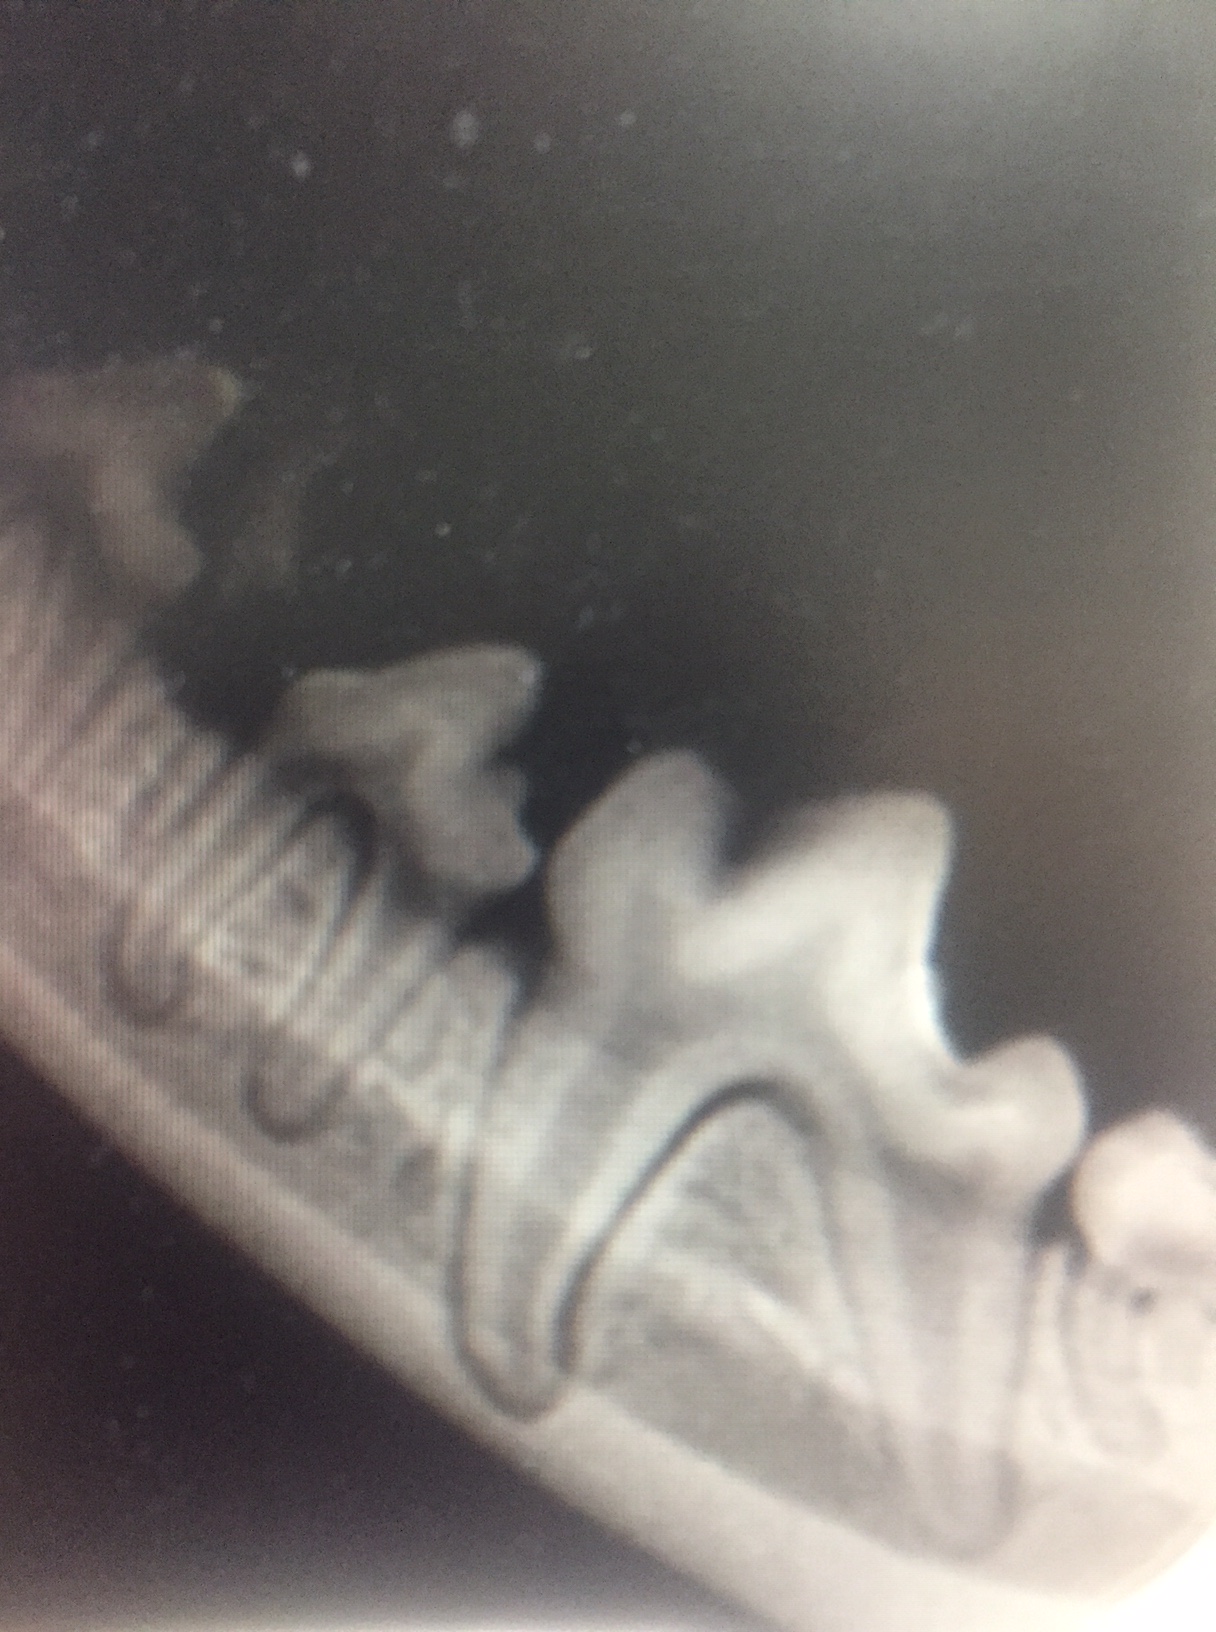

Chihuahua multiple deciduous teeth removed